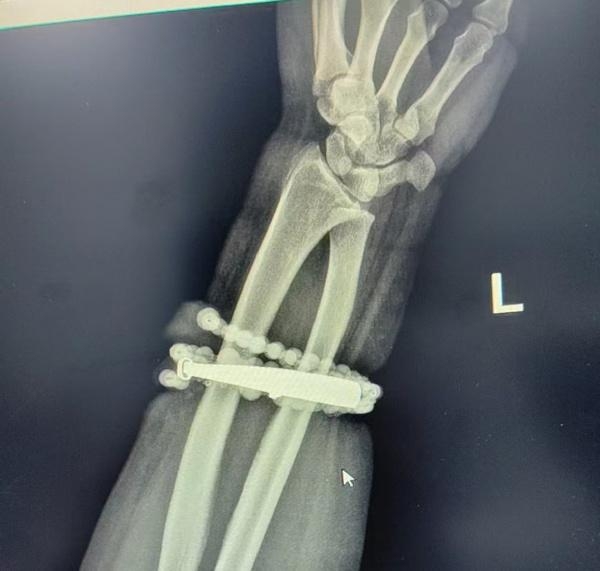

至日前龔女手腕處疼痛和紅腫症狀惡化,甚至流出膿汁,她這才就醫,經檢查後醫生發現部分銀手鐲和佛珠已嵌進龔女的肉裡,無法摘下,加上誘發嚴重感染、增生肉芽組織,需要立即為她進行手術。

經過1個多小時的手術,醫生順利將手鐲和佛珠從龔女手腕處增生組織中剝離,並清創爛肉和用藥控制感染。龔女術後恢復良好,已出院回家。

經約一小時手術處理,醫師順利將手鐲及串珠從增生組織中剝離,並進行清創與引流。(圖/翻攝自微博)